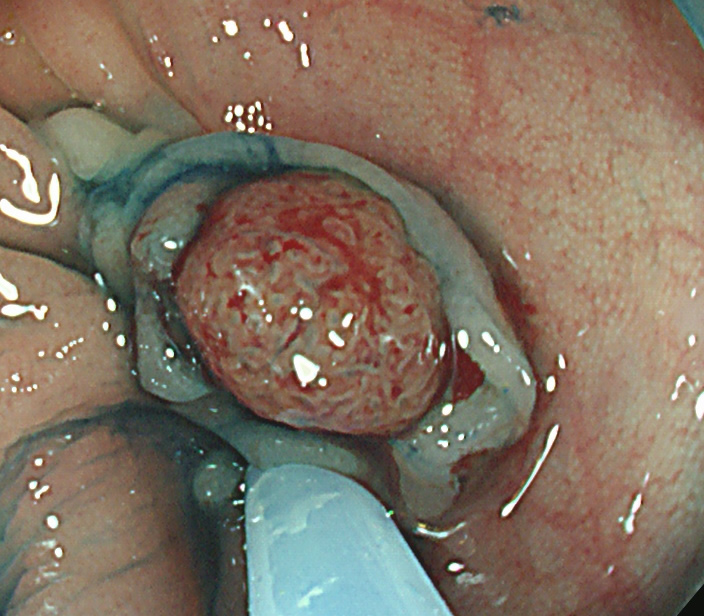

Extended Cold法法で切除された検体は「目玉焼き」のようになります。「黄身」が病変で、「白み」が周囲の正常組織(余白、マージン)です。

腫瘍の取り残しを防ぐために「白み(余白)の大きな目玉焼き」にすることが、最大のポイントです。